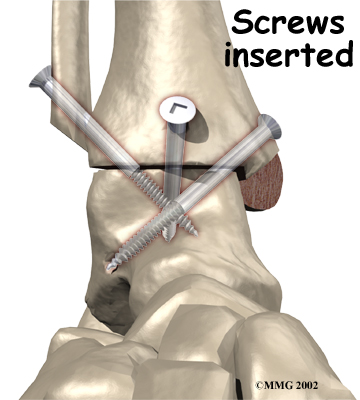

Several different operations have been developed to perform an ankle fusion. The basic procedure in each operation remains the same, however. The most common way that an ankle fusion is done is by making an incision through the skin to open the joint. Once the joint is opened, the surgeon uses a surgical saw to remove the articular cartilage surfaces of the ankle joint. Once the articular cartilage is removed on both sides of the joint, the body will try to heal the two surfaces together just as if it were fractured or broken.

It is important when the surfaces are removed that the angles of the cut surfaces are correct. When the tibia is brought against the talus, the foot should be at a right angle to the lower leg. Once the cuts are made the bones must be held in place while they fuse. This can be done using large metal screws and metal plates if necessary. The screws are usually under the skin and are not removed unless they begin to rub and cause pain.

Inserting the screws